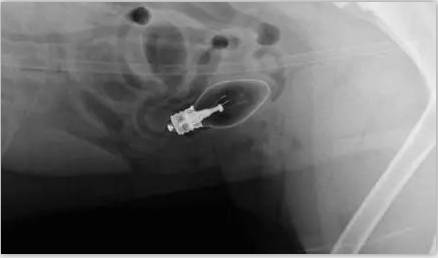

而只有拍片的时候你才知道狗狗的肚子里到底有什么东西,所以如果狗狗吃了什么奇怪的东西导致拉肚子,宠物医生肯定第一件事就是让你去拍片。

这天回家她发现家里的二哈突然开始拉肚子,连断食都没有用。然后她发现鞋柜上的臭袜子少了一只,在加上狗狗在成长期现在很喜欢咬东西磨牙,狗主人马上反应过来狗狗是因为将袜子吃掉后生病拉肚子。

为什么狗狗喜欢这种重口味的东西?现在看来是没办法了,只有去医院看看。狗主人带着二哈到了家附近的宠物诊所说,医生看完后表示要拍片,现在宠物主人只有一个想法,